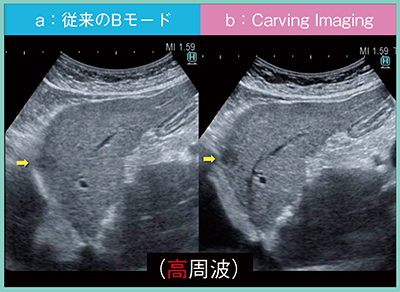

症例1は,78歳,女性,非アルコール性脂肪性肝炎(NASH)から肝硬変を来し,これまでに計3つの肝細胞がんに対してラジオ波焼灼療法(RFA)を繰り返している。さらに,2018年11月に認めた小さな低エコー結節が,2019年3月には9mmにまで増大していた。この低エコー結節は,従来のBモードでは見落とす可能性もあるが(図2 a),Carving Imagingでは必ず目にとまるレベルで描出されている(図2 b)。肋弓下からのあおり走査でも,Carving Imagingでは病変をはっきりと指摘でき,さらに,高周波プローブを使用することで,病変がきわめて明瞭となった(図3)。このように,Carving Imagingを用いることで,小病変でも病変構造の視認性が向上することがわかる。

図3 症例1:高周波プローブによる従来のBモードとCarving Imagingの画像比較